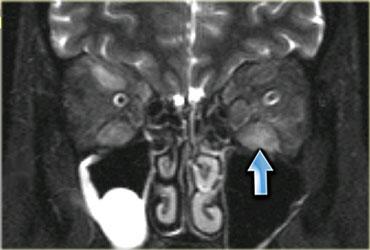

Hình bên trái là một bệnh nhân viêm cơ thể vùi.

Lưu ý tổn thương đối xứng của cơ tứ đầu đùi và sự vắng mặt của phù nề ở các tổ chức xung quanh.